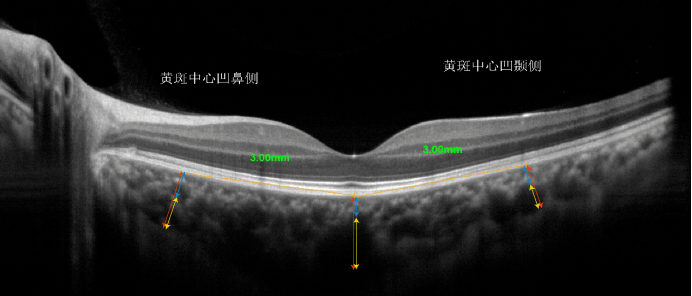

中心凹下脉络膜厚度测量示意图

对侧眼黄斑中心凹下,距黄斑中心凹3mm鼻侧及颞侧注:图中红色箭头耸揪